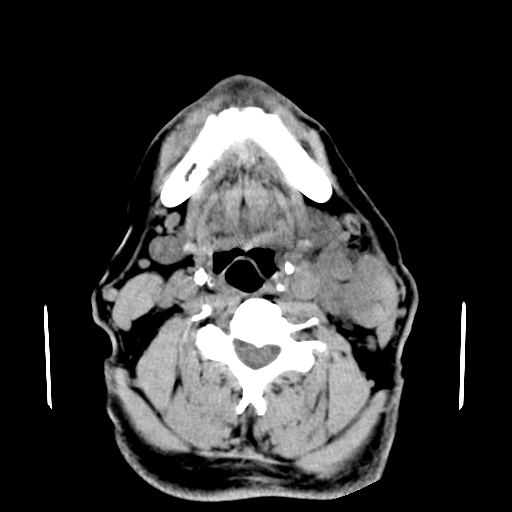

以下是引用卜一在2007-8-6 21:23:00的发言:[br]定位:左侧胸锁乳突肌内侧 颌下腺下后方。特征:弥漫性生长 软组织密度肿块,界限不清,内隐约见低密度坏死。考虑:神经源性肿瘤或血管源性肿瘤。

以下是引用wangzhanshuang在2007-8-6 21:08:00的发言:[br]腮腺混合瘤